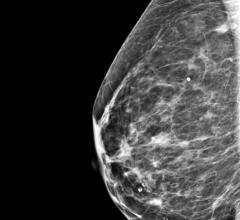

May 19, 2022 — According to ARRS’ American Journal of Roentgenology (AJR), axillary lymphadenopathy detected by breast ...

Despite decades of progress in breast imaging, one challenge continues to test even the most skilled radiologists ...

May 18, 2022 — Therapixel, a company leading the use of AI-based software for women’s health, announces it has released ...

May 16, 2022 — iCAD, Inc., a global medical technology leader providing innovative cancer detection and therapy ...